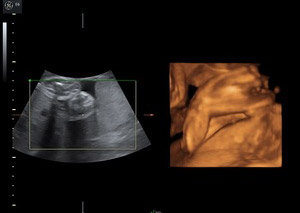

W nowoczesnych wysokiej klasy aparatach ultrasonograficznych istnieje możliwość przetwarzania danych z badania dwuwymiarowego co umożliwia pokazywanie obrazów trójwymiarowych badanych struktur płodu w czasie rzeczywistym.

Ultrasonografia trójwymiarowa 3D pozwala na uzyskanie statycznych obrazów przestrzennych, które otrzymywane są w procesie obróbki komputerowej danych z badania dwuwymiarowego. Ultrasonografia 4D pozwala na uwidocznienie dynamicznego przestrzennego obrazu.

Ta nowa prezentacja (prezentacja 4D) pochodzi od dodania czwartego wymiaru jakim jest czas. Badanie płodu metodą 4D pozwala nie tylko na obrazowanie przestrzenne płodu ale również pozwala na obserwację ruchów twarzy, obserwację otwierania i zamykania oczu, ruchów języka, ssania palców. Przy korzystnym ułożeniu płodu, w odpowiednim wieku ciążowym ( najlepiej pomiędzy 15. a 35. tygodniem ciąży) możliwa jest diagnostyka szeregu wad rozwojowych płodu. Badanie 4D pozwala też na precyzyjne obrazowanie rozwoju płodu i umożliwia podejrzenie wyglądu dziecka, którego wygląd jest niemal identyczny z jego rzeczywistym wyglądem.

Zastosowanie techniki 3D i 4D ma szczególne zastosowanie w położnictwie. Umożliwiają precyzyjną ocenę narządów wewnętrznych płodu, np. serca, mózgowia, kręgosłupa, twarzy oraz w sposób istotny pozwalają na zwiększenie wykrywalności wad budowy płodu .